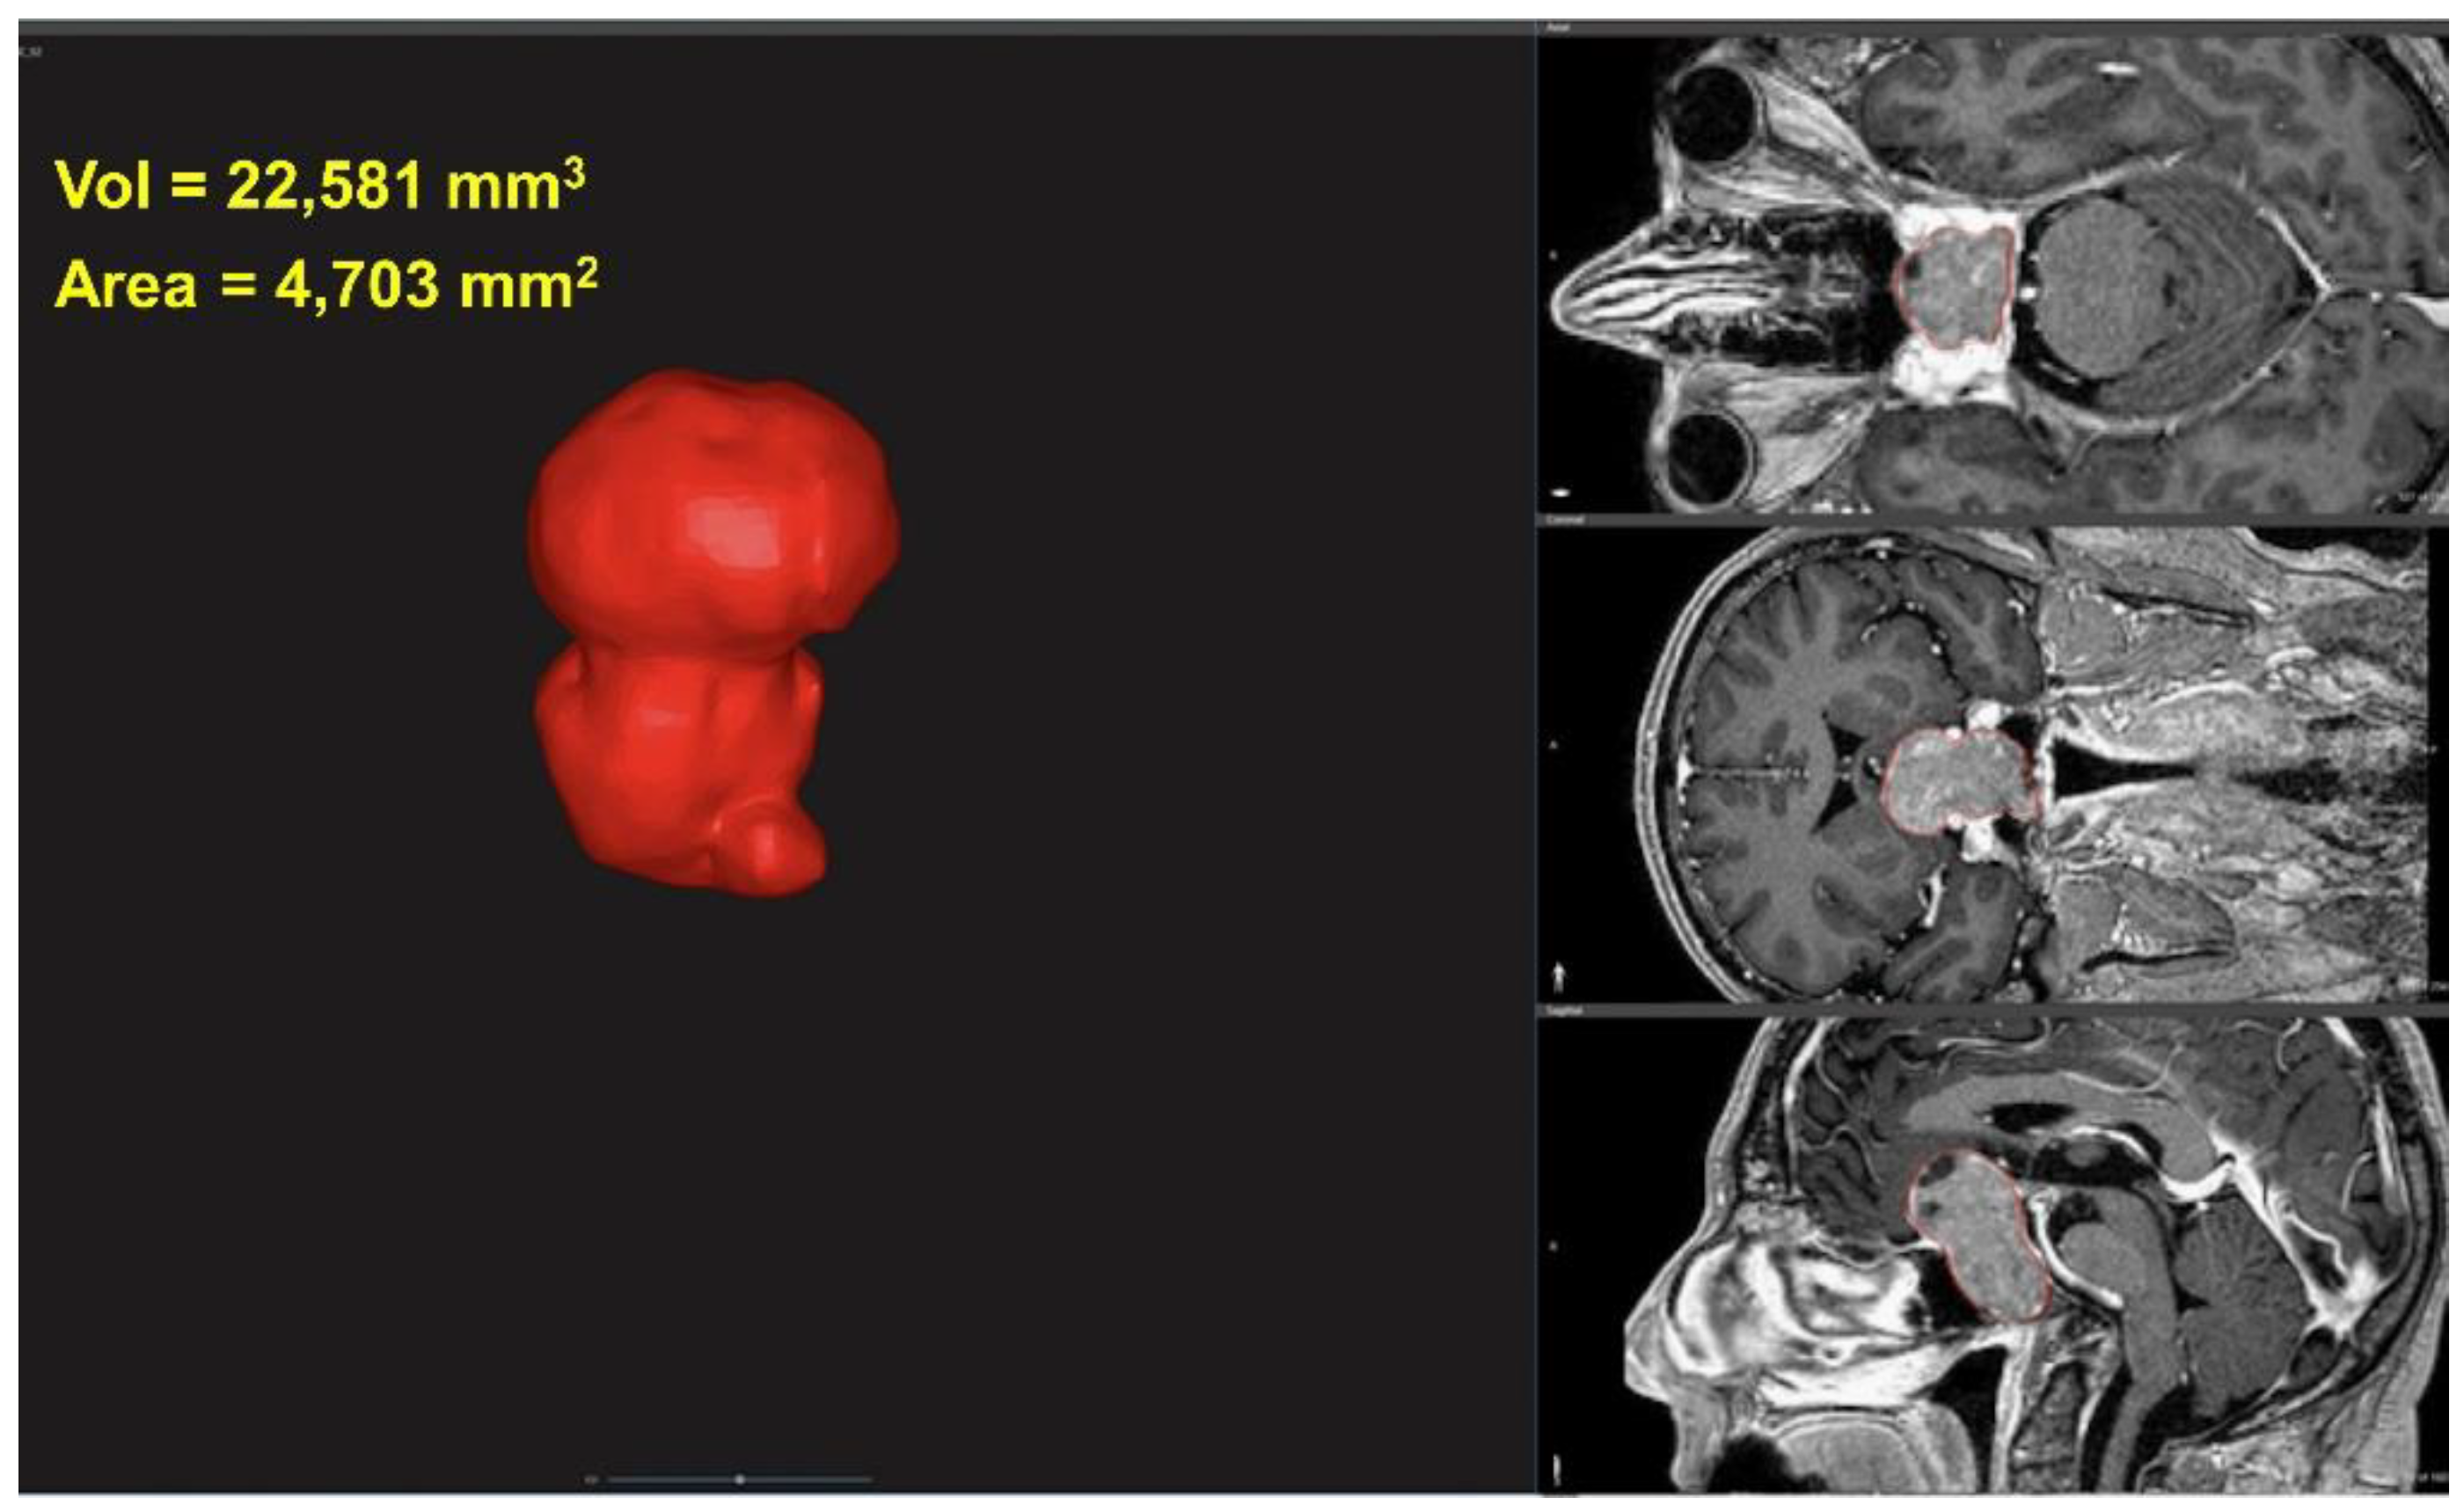

2.2. 3D Characterization of Tumor

2.3. Tumor Volume and Area